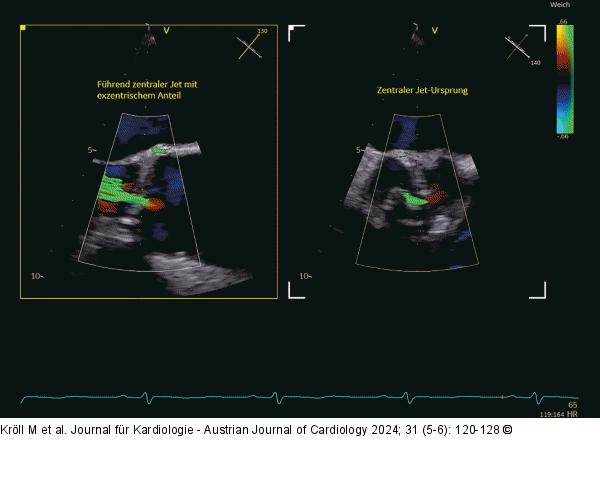

Abbildung 4: Echo 2D-TEE, biplane Darstellung mit Farbdoppler, nicht relevante AI bei degenerativ veränderter BAK |

2D-TEE, biplane Darstellung mit Farbdoppler, nicht relevante AI bei degenerativ veränderter BAK |